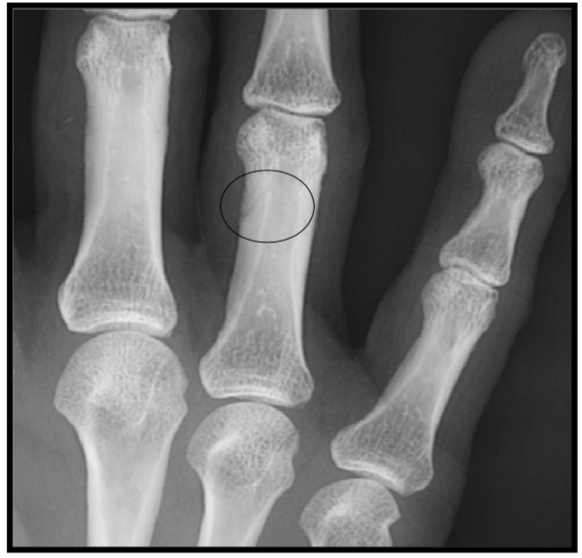

Nutrient vessel entrance

variation anat normal